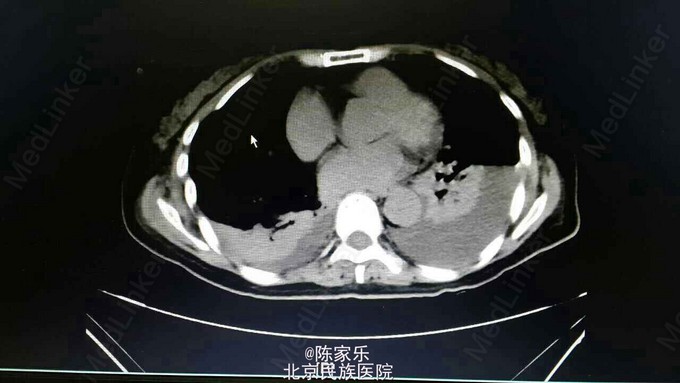

主诉:上腹部疼痛伴呕血2小时 现病史:女,55岁,2小时前无明显诱因突发上腹部疼痛,疼痛无向他处放射,伴恶心、呕暗红色血,量血100ml,无腹胀、腹泻、头晕、心季等不适。 既往史:1个月前因胰头癌行胰十二指肠切除术。否认高血压、糖尿病、肝炎、胃溃疡病史。

查体:腹部平软,上腹部轻压痛,无肌紧张、反跳痛。 实验室检查:未见明显异常 CT:胰十二指肠切除术后改变,肝门区及肝周积液,肝右叶近包膜区低密度灶,肝内胆管轻度扩张。